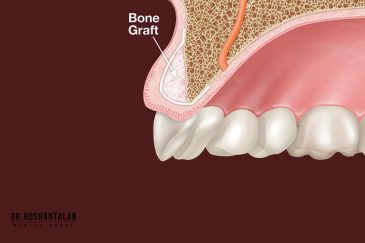

🔸جراحی پیشرفته نظیر سینوس لیفت